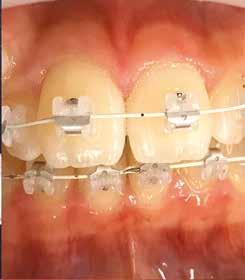

Szemfog mezializációt követően történik az approximális felszínek igazítása. Elérjük a megfelelő mezio-disztális szélességet, és a kontaktpont incizális irányba helyeződik át. Ebben a fázisban mindig szükséges egyeztetni az esztétikai pótlást készítő fogorvossal a szükséges szemfogformáról és a későbbi felépítmény pontos helyzetéről. Az esztétikai fogorvosnak kell eldöntenie a meziális és disztális felszínek elcsiszolásának mértékét is.

3. a–b ábra: .019x.025” acél mint befejező fogszabályozóív vesztibuláris hajlításokkal a 11-13., a 21-23., valamint a 24-25. és a 14-15. fogak között. 4. a-b. ábra: A szemfog palatinális felületének formázása (a, Rodentica 257) és polírozása narancssárga Sof-Lex koronggal (b). A braketeket már eltávolították ezekről a fogakról.